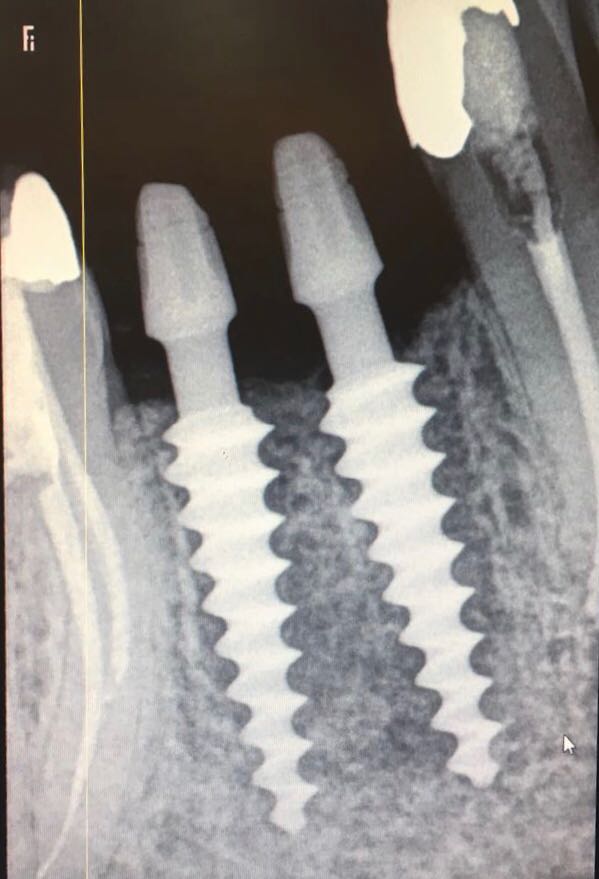

•  DENTAL IMPLANTS